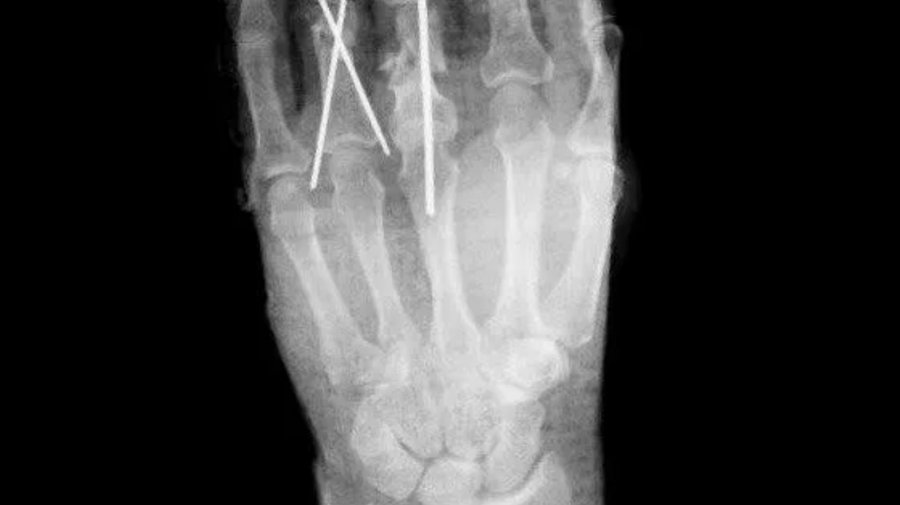

«После хирургической обработки ран мы зафиксировали пальцы в функционально выгодном положении при помощи спиц. Затем восстановили сосуды, сшили вены, артерии, тем самым восстановили функции конечности. Операция прошла успешно и заняла около 2,5 часов», – рассказал заведующий травматологическим отделением Константин Смирнов.

Своевременное вмешательство помогло успешно провести реплантацию пальцев, сохранив пациенту подвижность кисти. Сейчас мужчина чувствует себя хорошо и будет выписан после реабилитации.